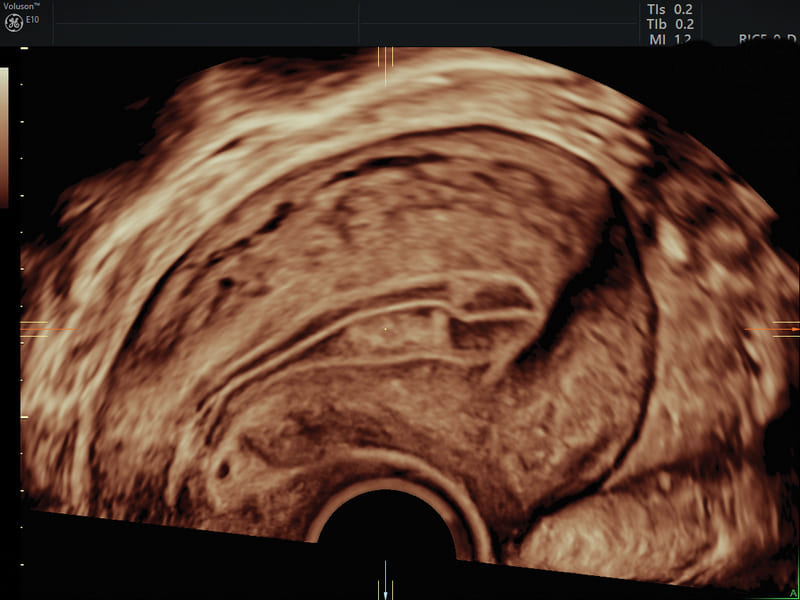

SonoPelvicFloor: grazie all’AI, SonoPelvicFloor semplifica il processo dell’esame 3D automatizzando l’allineamento del piano e le misurazioni, offrendo indicazioni sul flusso di lavoro per eliminare l’incertezza e migliorare l’efficienza.